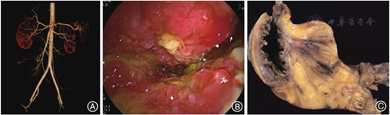

影像学检查:入院后给予禁食和静脉补液后患者腹痛缓解、肛门排气恢复,遂行全腹CT平扫加增强,显示右中下腹局部小肠肠壁水肿增厚,增强后明显充血,周围脂肪间隙浑浊伴多发渗出,见一3.5 cm × 4.1 cm的不规则软组织团块影,见图1A、1B;病变肠管周围多发扩张、迂曲血管影,见图1C;病灶近端肠管扩张,远端肠管内见多量液体。肠系膜上动脉CTA示动脉走行良好,未见充盈缺损或瘤样扩张,见图2A。

小肠镜检查:空肠中下段查见一处溃疡上覆白苔,此处管腔狭窄、周围黏膜息肉样增生,内镜无法通过,见图2B;近端肠管扩张伴大量积液,结直肠未见异常。空肠中下段溃疡边缘活检示活动性慢性肠炎伴幽门腺化生,黏膜层毛细血管未见异常,未见肿瘤及其他特异性组织学改变。

术后病理大体观察:切除小肠57 cm,距远端切缘20 cm处局部肠腔狭窄,狭窄段长约8 cm,此处肠黏膜呈灰褐色伴不规则溃疡及周围黏膜颗粒状增生,肠壁增厚伴肠系膜脂肪结节状增生、包绕,范围约7.0 cm × 7.0 cm × 3.5 cm,见图2C。肠管狭窄处至近端切缘之间肠管扩张、肠壁菲薄,散在肠黏膜糜烂。肠周查见淋巴结18枚,最大径0.5 ~ 2.0 cm。